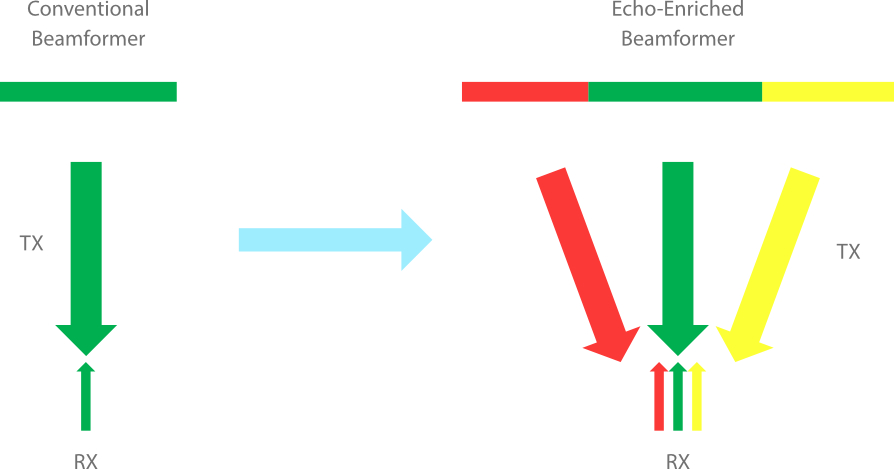

Echo-enriched Beam Forming

Traditionally neglected echo signals of adjacent beams are formed into one finer, stronger imaging beam. This provides better ŌĆśout-of-focusŌĆÖ image resolution and deeper image penetration.